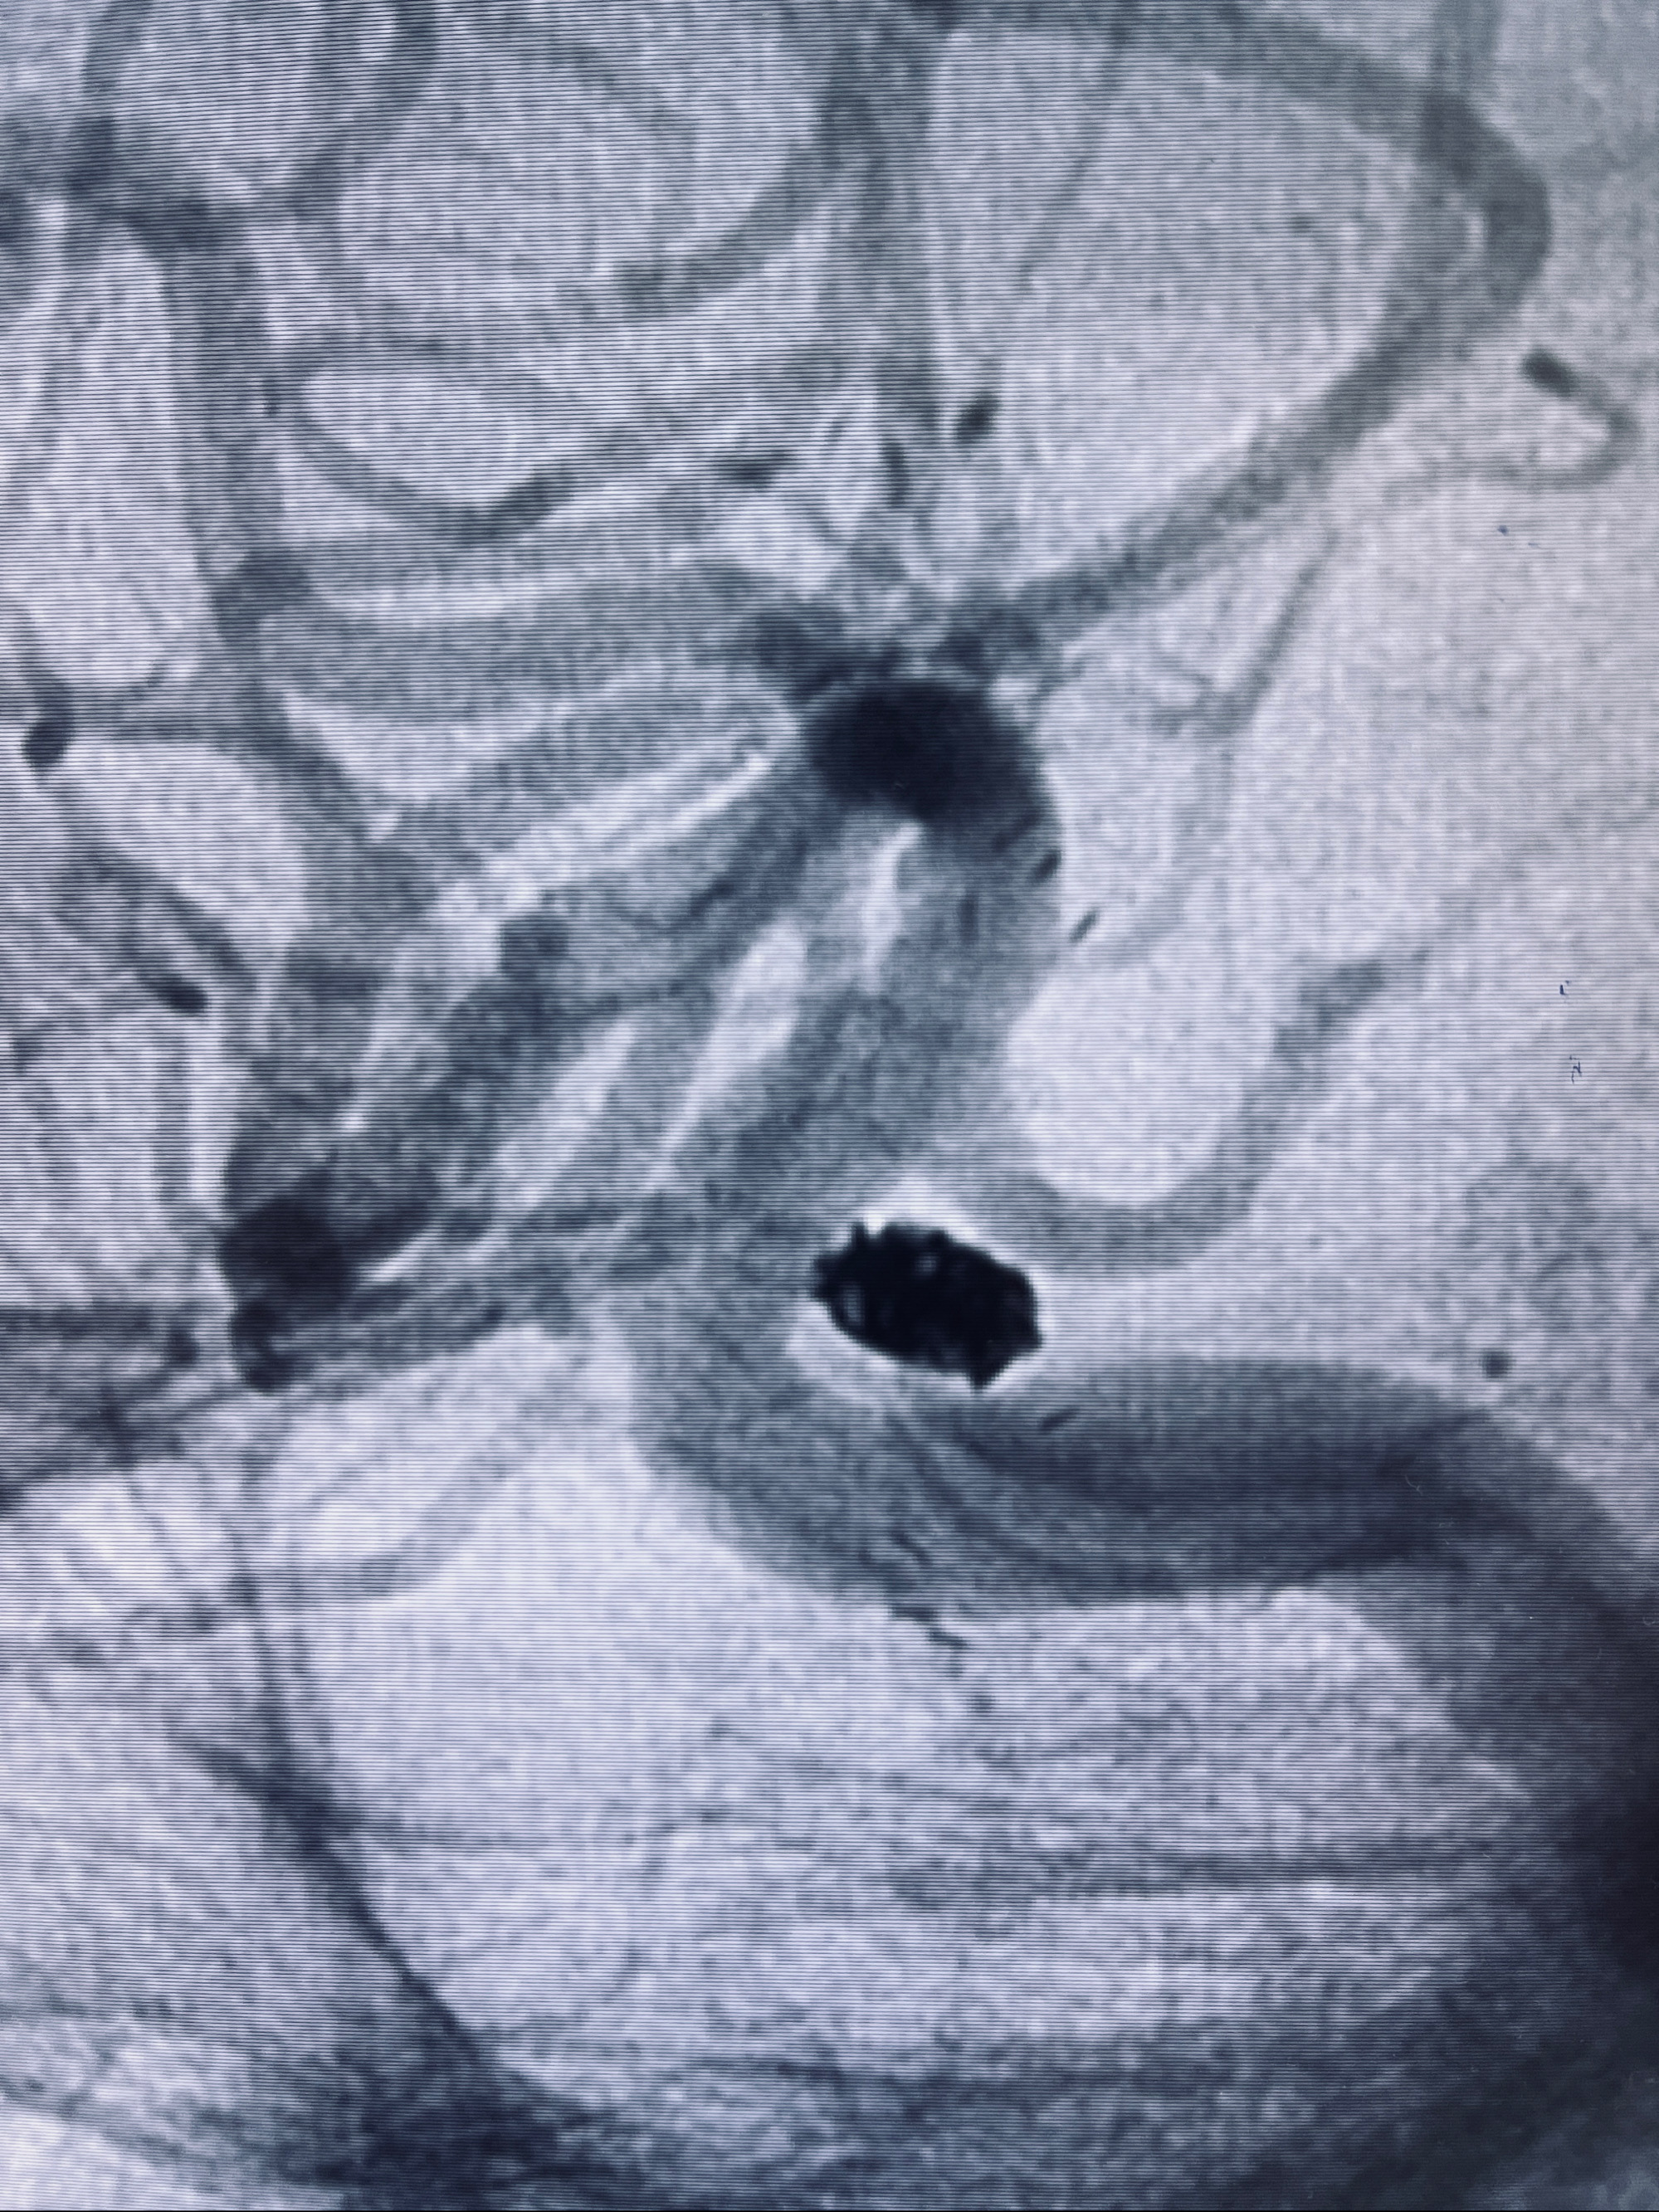

2022-09-29复查DSA